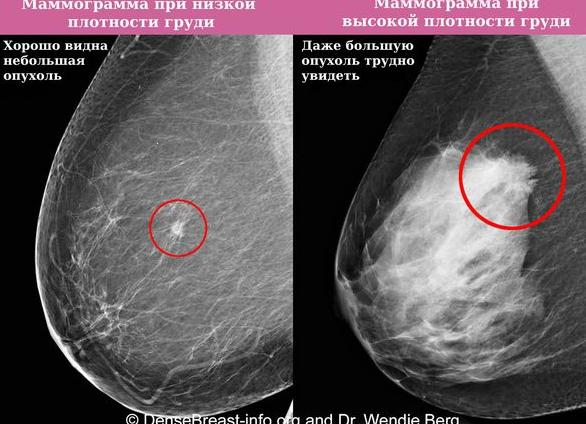

Маммография

После 35 лет всем женщинам надо 1 раз в 2 года делать маммографию. Рентгеновское исследование является эффективным методом скрининга предрака и рака груди. Для эффективной оценки R-картины используется специальная классификация Bi-Rads, которая предусматривает распределение всех рентгенологических картин на 7 вариантов – от 0 до 6. Оптимальный результат маммографии – bi-rads 1, указывающий на нормальную структуру железистой ткани. Для фиброзно-железистой инволюции используется категория bi-rads 2, являющаяся вариантом нормы для женщин в возрасте перименопаузы. К основным R-признакам возрастных изменений относятся:

• значительное уменьшение железистых структур;

• преобладание жировой и фиброзной ткани;

• наличие соединительнотканных тяжей;

• отсутствие узловых и крупных кистозных структур.

Нельзя отказываться или игнорировать рекомендации врача по регулярному проведению маммографии – методика помогает своевременно обнаружить первые проявления предраковых нарушений в груди.